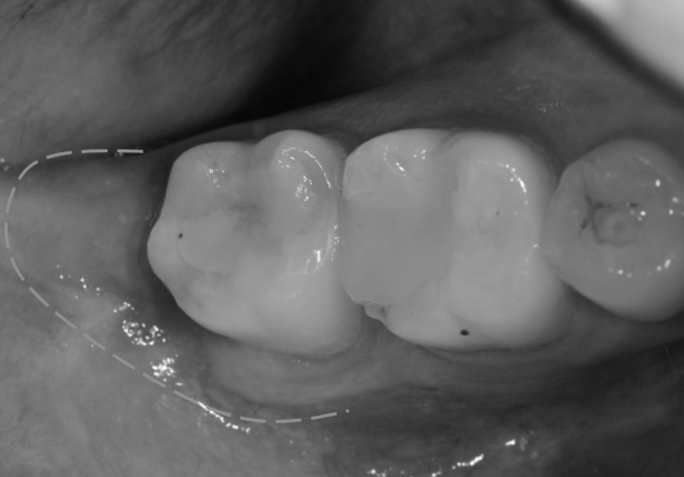

발치 후 구멍

사랑니 발치 후 피덩이(혈병)

많은 분들이 빈공간 안에 있는

피딱지, 피덩이를 보고 떼어내야 하나 생각하십니다.

그러나 이 피덩이 또한 회복하는 과정 중

발치 후 초기에 자연스럽게 형성되는 혈병(혈전)으로,

출혈을 막고 상처를 보호하는 역할을 합니다.

피덩이(혈병)이 표시되어 있다.